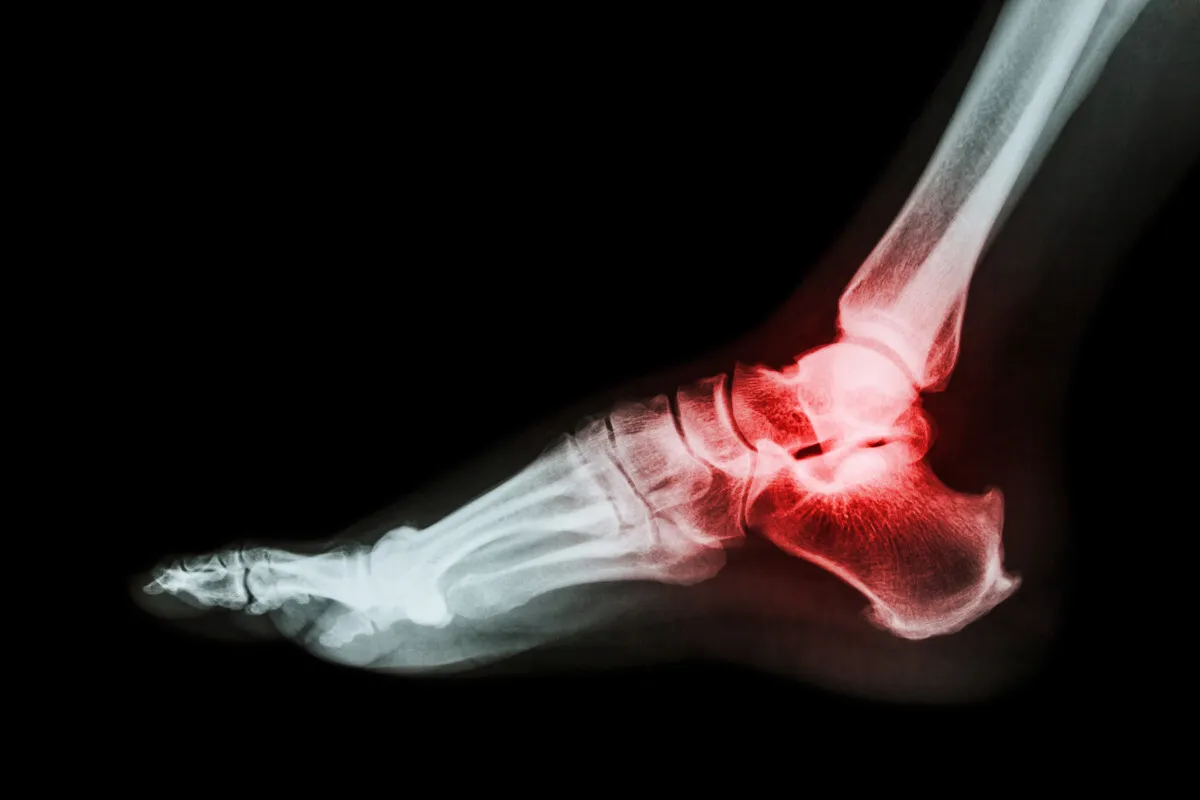

Kość piętowa, czyli pięta (łac. calcaneus), to największa kość stępu, która odgrywa fundamentalną rolę w biomechanice stopy. To właśnie ona stanowi główny punkt podparcia dla ciężaru ciała podczas stania i chodzenia, a także działa jak dźwignia dla mięśni łydki, umożliwiając ruchy stopy. Jej skomplikowana budowa i strategiczne położenie sprawiają, że jest niezwykle ważna dla stabilizacji i amortyzacji. Złamanie kości piętowej jest najczęściej wynikiem urazów o dużej energii kinetycznej, takich jak upadki z wysokości (np. z drabiny, balkonu) czy wypadki komunikacyjne. Siła uderzenia przenosi się przez kość piętową, często prowadząc do jej rozkruszenia. Ze względu na jej kluczową funkcję i złożoną budowę, złamanie pięty jest uważane za jeden z najcięższych urazów stopy, a jego leczenie i rehabilitacja są procesem długotrwałym i wymagającym.

Złamania kości piętowej mogą przybierać różne formy, od prostych pęknięć bez przemieszczenia, po skomplikowane urazy wieloodłamowe, gdzie kość rozpada się na wiele fragmentów. Wyróżniamy złamania pozastawowe, które nie obejmują powierzchni stawowych, oraz złamania przezstawowe, które uszkadzają stawy między kością piętową a innymi kośćmi stępu. Te ostatnie są szczególnie problematyczne, ponieważ mogą prowadzić do uszkodzenia chrząstki stawowej i późniejszych powikłań, takich jak choroba zwyrodnieniowa. Im bardziej złożone złamanie zwłaszcza wieloodłamowe i przezstawowe z przemieszczeniem odłamów tym dłuższy i bardziej skomplikowany będzie proces leczenia i rehabilitacji. Takie urazy często wymagają precyzyjnej rekonstrukcji chirurgicznej, aby przywrócić prawidłową anatomię i funkcję stopy.